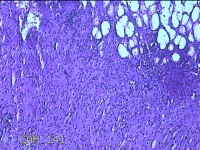

大网膜

性别

女

年龄

44岁

临床诊断

1.双侧输卵管炎 2.子宫肌瘤 3.宫内节育器

一般病史

下腹痛3月。

标本名称

大体所见

灰白暗红色组织5.5z4.5x1.3cm一块,表面糜烂。